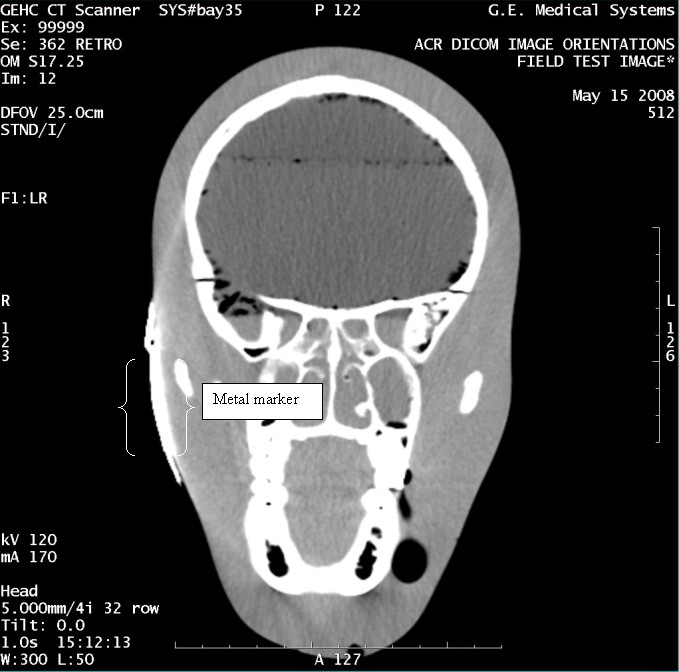

- With the support of the site personnel, examine the images sent

to the Review Station (i.e., 12 series, each with 1 image) and compare

their orientation to the images in this document.

- Each image contains a metal marker on the phantom's right cheek.

- Each image in this document contains a description of the expected

orientation of the metal marker (i.e. to prove Left and Right) as

well as the Posterior and Anterior orientation description.note:

The sample images included in this document use “R”, “L”, “P”, and “A” for “Right”, “Left”, “Posterior” and “Anterior” orientation. The Hospital Review Station may use a different style of annotation. The style used is not relevant to this procedure.

- Each image in this document has sufficient space to store the observed results for up to 4 Review Stations.

- Enter ‘Y’ in the space to indicate the observed result matches the expected.

- Enter ‘N’ in the space to indicate the observed result does not match the expected.

- Enter “NA” in the space if a column is not being used.

- Repeat for each destination.

Figure 14. Exam 99999, Series 362